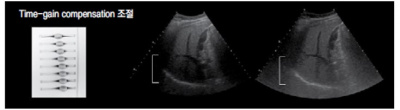

기본적인 영상 조절 ⑤ : 시간-게인 조절(TGC)

시간-게인 조절장치는 특정 깊이의 에코를 선택적으로 조절하여, 원하는 부위의 영상의 밝기를 조절하는 데 사용되며 일반적으로 TGC라 부른다. 음파가 탐촉자에서 멀어질수록 감쇠현상에 의해 강도가 현저히 떨어져 화면에 가까운 곳은 밝게, 먼 곳은 어둡게 나타나게 되므로 초음파 기계에서 자동적으로 TGC control을 해준다. 하지만, 추가적으로 수동 시간-게인 조절장치를 이용하여 먼 곳의 정보를 선택적으로 증폭시켜 밝기를 조절할 수 있다.